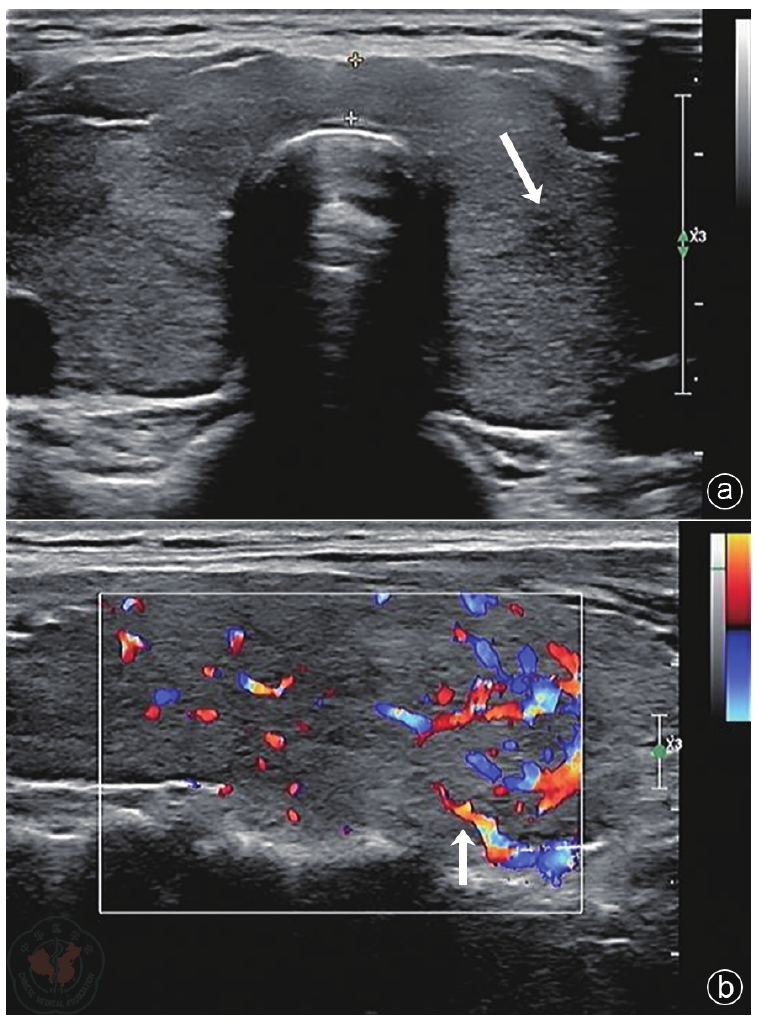

图2 毒性弥漫性甲状腺肿合并桥本甲状腺炎患者骨髓组织涂片注:大部分为脂肪组织,造血组织容量30%,脂肪组织70%,呈骨髓增生低下。造血组织粒、红系增生低下,两系以中、晚阶段细胞为主,散在或小堆可见。巨核细胞未见。淋巴细胞散在可见,偶见小堆,浆细胞散在可见。嗜酸性粒细胞散在可见。未见纤维化(HE 10×40)

患者33岁,初诊时甲状腺功能显著亢进,游离三碘甲状腺原氨酸(16.23 pmol/L)、游离甲状腺素(45.38 pmol/L)水平升高,促甲状腺激素水平低下(0.006 U/L),促甲状腺激素受体抗体及甲状腺过氧化物酶抗体阳性,甲状腺摄碘率增高(2 h 49.40%,6 h 80.90%,24 h 94.10%)。超声提示甲状腺轻度肿大、实质回声弥漫性减低不均且血流稍丰富,符合GD病合并桥本甲状腺炎表现,且伴粒细胞减少。予以甲巯咪唑治疗后,患者出现骨髓抑制(表现为粒细胞缺乏、红细胞及血小板减少),继发急性化脓性扁桃体炎,并诱发甲亢危象(BWPS评分45分)。骨髓活检提示造血组织增生低下,关键免疫学检查发现抗核抗体(≥1∶160)及抗Sm抗体阳性,考虑DILE所致血液系统损害。停用甲巯咪唑,经积极抗感染,应用重组人粒细胞刺激因子、糖皮质激素、免疫抑制剂及后续碘-131治疗后,患者感染控制,血常规逐渐恢复正常。甲状腺功能于碘-131治疗后转为亚临床甲减,补充左甲状腺素钠片后恢复正常。患者DILE相关指标(抗核抗体滴度)下降,糖皮质激素及免疫抑制剂用量减少,病情稳定。

The patient, a 33-year-old woman, presented with significant hyperthyroidism at initial diagnosis, characterized by elevated levels of free triiodothyronine (FT3) (16.23 pmol/L) and free thyroxine (FT4) (45.38 pmol/L), decreased thyroid-stimulating hormone (TSH) levels (0.006 U/L), positive thyrotropin receptor antibody (TRAb) and thyroid peroxidase antibody (TPOAb), and increased thyroid iodine uptake (2 h 49.40%, 6 h 80.90%, 24 h 94.10%). Ultrasonography revealed a mildly enlarged thyroid with diffuse heterogeneous hypoechogenicity and slightly increased vascularity, consistent with the clinical presentation of GD complicated by HT, accompanied by granulocytopenia. Methimazole therapy induced myelosuppression (characterized by agranulocytosis, anemia, and thrombocytopenia), leading to secondary acute suppurative tonsillitis and triggering a thyroid storm (BWPS score 45). A bone marrow biopsy revealed hypoplasia of hematopoietic tissue. Key immunological tests were positive for antinuclear antibodies (≥1∶160) and anti-Sm antibodies, suggesting hematologic damage caused by DILE. After discontinuation of methimazole, aggressive antimicrobial therapy, administration of recombinant human granulocyte colony-stimulating factor (G-CSF), glucocorticoids, immunosuppressants, and subsequent I131 therapy, the patient′s infection was controlled. Complete blood count parameters gradually normalized. Thyroid function converted to subclinical hypothyroidism after I131 therapy and normalized with levothyroxine supplementation. DILE-related markers (antinuclear antibody titers) decreased, allowing for a reduction in glucocorticoid and immunosuppressive doses, and the patient′s condition remained stable.